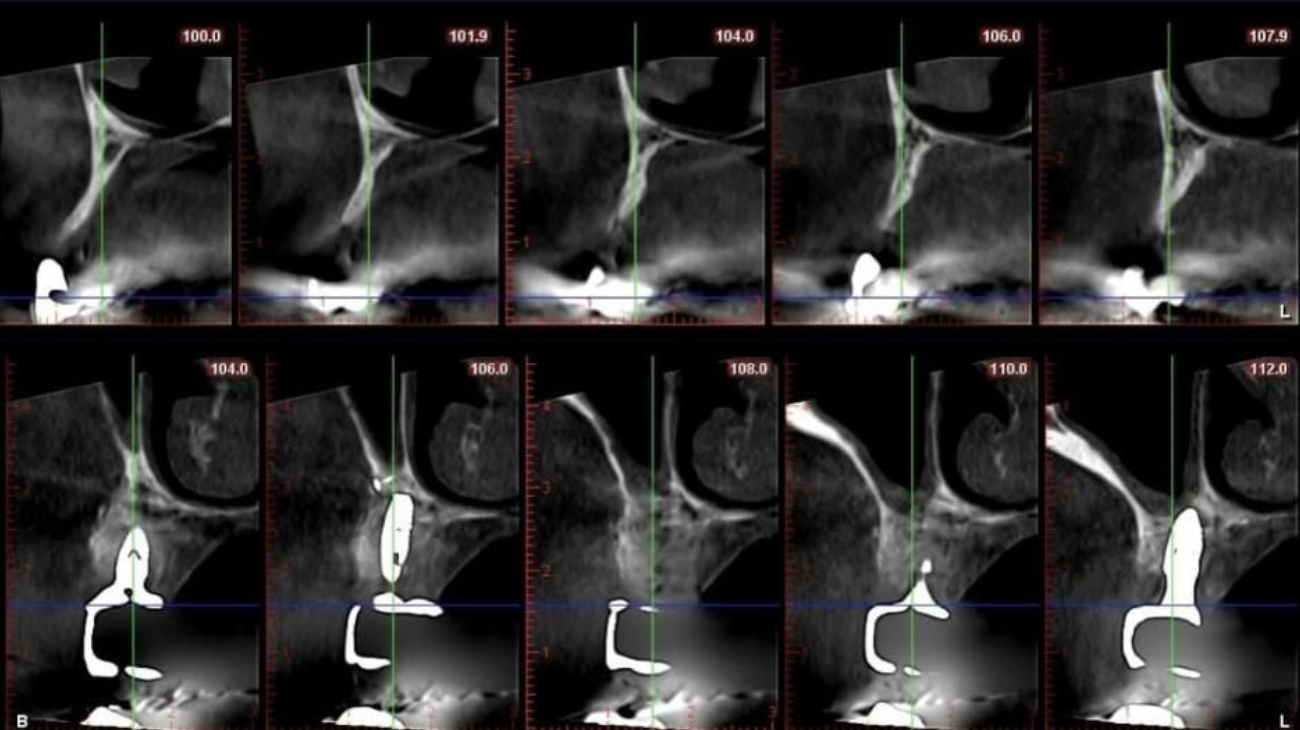

- Radiografii digitale şi CBCT (tomografii computerizate) pentru a măsura volumul și densitatea osoasă.

- Examinare clinică amănunțită a zonei unde se dorește implantul, pentru a identifica particularități anatomice (sinus maxilar, apropierea de nervi, etc.).